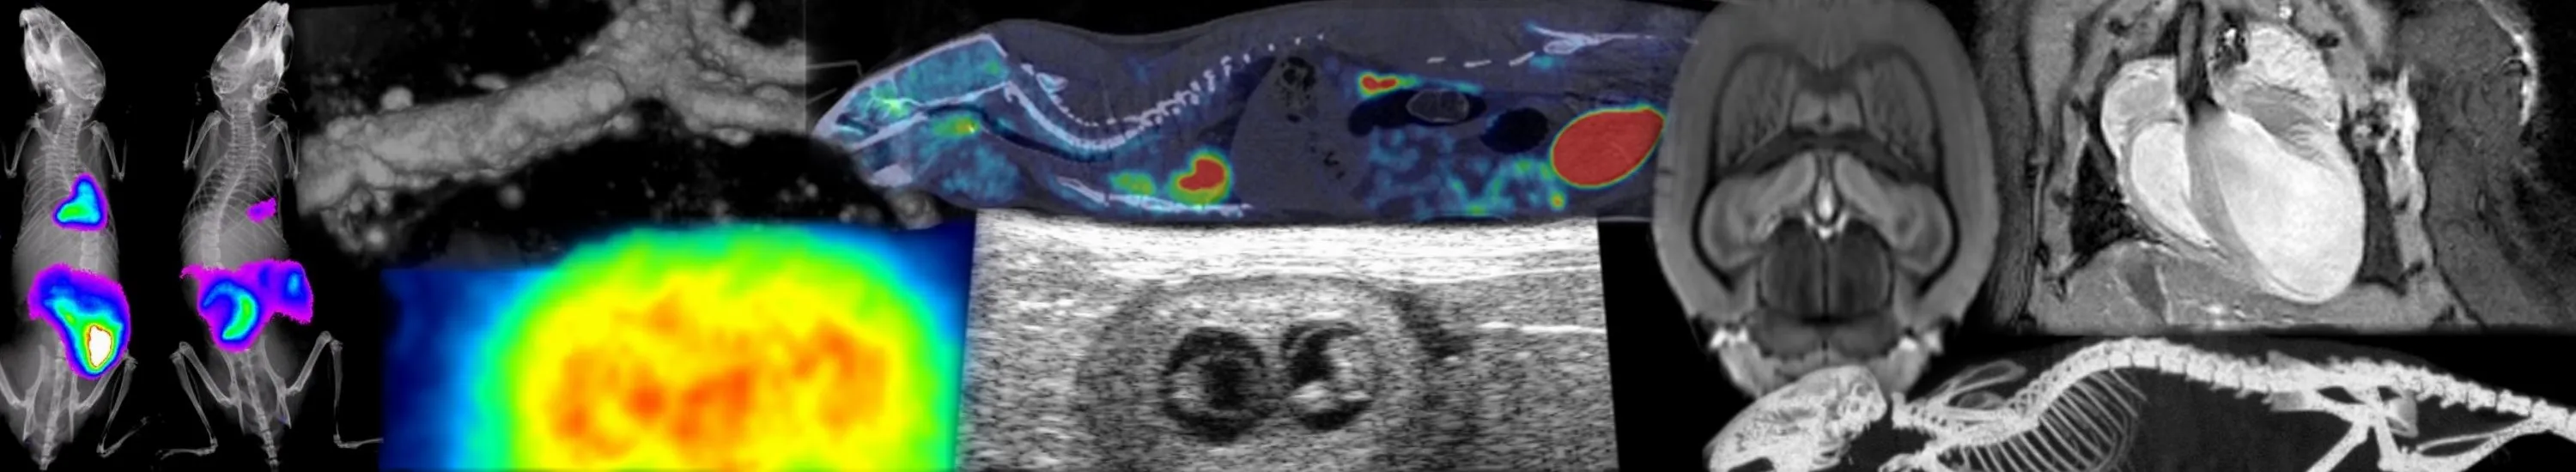

An overview of the research goals, current research projects, and principal investigators of the CINEMA research theme. Image The Cardiometabolic Imaging: New Methods and Applications (CINEMA) theme is a PI lead group of physicists, engineers, clinicians and biologists who work together, as well as across CVS themes and external collaborations, to generate disease modelling and novel imaging techniques that will ultimately improve diagnosis and future therapies. Non-invasive imaging techniques have revolutionised the ability to determine primary causes of cardiac, vascular and metabolic disease as well as the efficacy of potential therapies. The Cardiometabolic Imaging: New Methods and Applications (CINEMA) theme is a PI lead group of physicists, engineers, clinicians and biologists who work together, as well as across CVS themes and external collaborations, to generate disease modelling and novel imaging techniques that will ultimately improve diagnosis and future therapies. The CINEMA theme members collaborate across the CVS research themes and beyond to develop and provide state-of-the are in vivo imaging and modelling to our users and collaborators. Our members are currently pursuing the following research priorities: (Injectable) Biomarker development Hardware and software development Image analysis, big data and modelling In vivo imaging and modelling of humans and animals can provide important information on structure and function of different organs in a non invasive manner. Under the umbrella of Edinburgh Imaging, many CVS members use the excellent preclinical (Edinburgh Preclinical Imaging) and clinical (CRIC - Edinburgh Imaging Facility QMRI and BRIC - Edinburgh Imaging Facility WGH) facilities to generate state-of the art imaging protocols to determine novel biomarkers and therapies for their respective fields. Edinburgh Imaging Edinburgh Preclinical Imaging CRIC - Edinburgh Imaging Facility QMRI BRIC - Edinburgh Imaging Facility WGH CINEMA Research Projects Current research projects within the research theme of Cardiometabolic Imaging (CINEMA) at CVS. CINEMA Research Groups A list of the current PI-led Research Groups within the CINEMA research theme. Magnetic Resonance Imaging (MRI) The Centre for Cardiovascular science has had a long tradition in innovation of cardiac imaging from Preclinical MRI informing clinical diagnostic techniques. These innovations have lead to major clinical trials (MA3RS study and EVOLVED TRIAL). Present preclinical MRI projects for clinical translation include are on novel manganese-enhanced imaging of the myocardium, measuring fibrosis and adverse cardiac remodelling under pressure overload in the mouse and cardiac 23Na MRI imaging to identify viability of myocardium after cardiac infarction and multimodality imaging of myocardial infarction. Further studies are investigating novel contrast agents in studies of Type 1 and Type 2 diabetes. MA3RS study EVOLVED TRIAL manganese-enhanced imaging of the myocardium cardiac remodelling under pressure overload cardiac 23Na MRI imaging of myocardial infarction novel contrast agents in studies of Type 1 and Type 2 diabetes Positron Emission Tomography (PET) CVS researchers lead a multicentre cohort study determine if 18F-PET imaging can identify high-risk vulnerable coronary artery plaques (SCOT-HEART trial). The Saltire 2 project will use PET/CT imaging to assess the potential for new treatments to halt the progression of aortic stenosis and reduce the need for valve replacement surgery. The preclinical PET researchers are developing new PET ligands: 18F-LW223 is a ligand that will identify cardiovascular inflammatory disease, improving on present ligands which are susceptible to polymorphisms (Detection of cardiovascular inflammation using PET) and an 18F-Proline probe for the identification of cardiac fibrosis activity (PET imaging biomarkers of fibrosis). Standardisation of preclinical PET protocols across PET scanners and PET facilities is essential to enable comparable data for crucial translation of data to human imaging. A cross country, multicentre analysis of PET/CT scanners and protocols is being carried out to achieve standardised protocols. SCOT-HEART trial Saltire 2 project Detection of cardiovascular inflammation using PET PET imaging biomarkers of fibrosis Standardisation of preclinical PET protocols High Definition Ultrasound High definition ultrasound is used to assess functional and structural outcomes from fetus through to adult. Present ongoing projects will identify the consequences of high and low glucocorticoid exposure on placental development and haemodynamic function. These studies will inform on the functional changes in feto-placental vasculature impacting on heart development and determine mechanisms whereby prenatal glucocorticoid exposure can underpin neonatal and adult cardiometabolic health. the consequences of high and low glucocorticoid exposure on placental development and haemodynamic function Research in a Nutshell Videos Prof Megan Holmes Prof David Newby Prof Carmel Moran Dr Scott Semple Dr Adriana Tavares This article was published on 2024-03-19